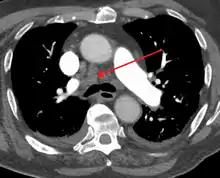

Some mediastinal structures on a chest radiograph.